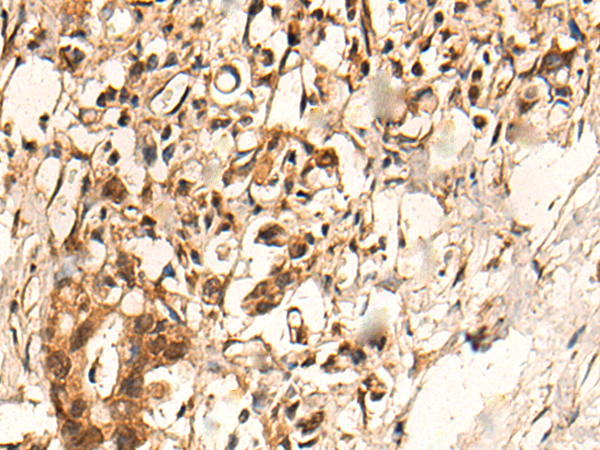

The image is immunohistochemistry of paraffin-embedded Human gastric cancer tissue using P04663(PFKFB4 Antibody) at dilution 1/35. (Original magnification: ×200) |